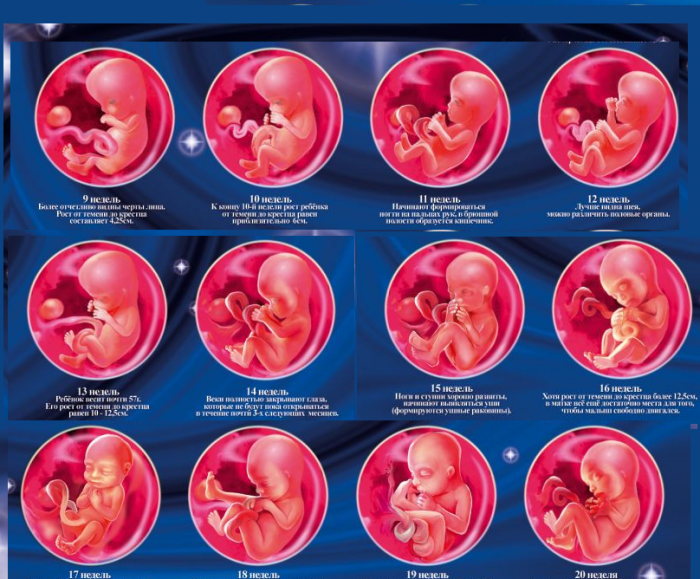

Развитие эмбриона: Что происходит на 3 неделе беременности

Раздел: Фотопанорама